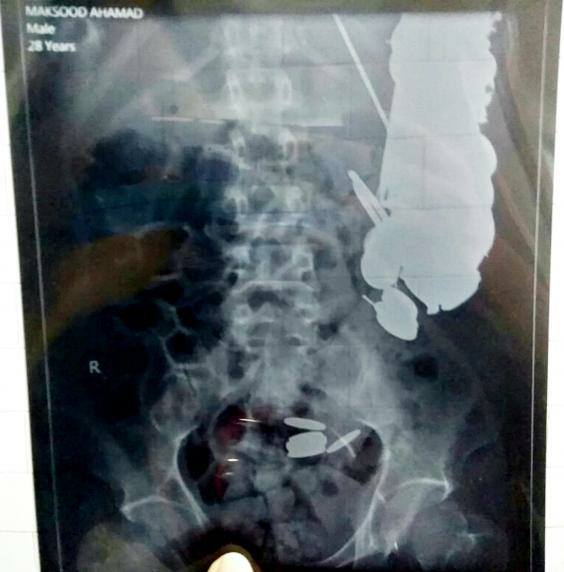

Maksud Khan es el nombre del paciente de 35 años que fue ingresado a un hospital de urgencia en la ciudad Madhya Pradesh (India) con un agudo dolor de estómago, debido a que a lo largo de su vida había ingerido siete kilos de monedas, clavos, vidrios, cuchillos y pedazos de hierro, entre otras cosas.

Cuando Khan fue derivado al recinto hospitalario los médicos que lo atendieron pensaban que se trataba de un envenenamiento por comida, pero tal fue la sorpresa cuando le realizaron la endoscopia que los especialistas decidieron intervenirlo de urgencia ante el peso de la evidencia de los exámenes.

Cuando los médicos empezaron a extraer los objetos no tradicionales encontrados en el estómago del hombre comenzaron las sorpresas, ya que tenía 263 monedas de distintos tipos, 100 clavos oxidados, dos docenas de cuchillas de afeitar, múltiples trozos de vidrios y un trozo de hierro de 15 centímetros.

Al pesar los objetos, la sorpresa tuvo un número redondo: 7 kilos de materiales extraídos, que el hombre había ingerido debido a que se consideraba un “adicto” a comer este tipo de objetos, asumiendo que padecía un serie trastorno alimentario desde hace varios años.

“Estamos impactados por descubrir lo que había”, dijo el Dr. Priyank Sharm del Hospital Sanjay Gandhi al periódico inglés The Independent, asegurando que nunca había visto un caso igual en todos los años que llevaba de profesión..